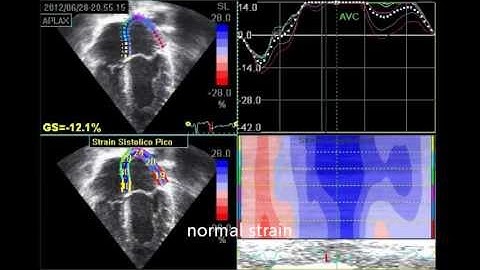

How and why to measure RV and LA strain